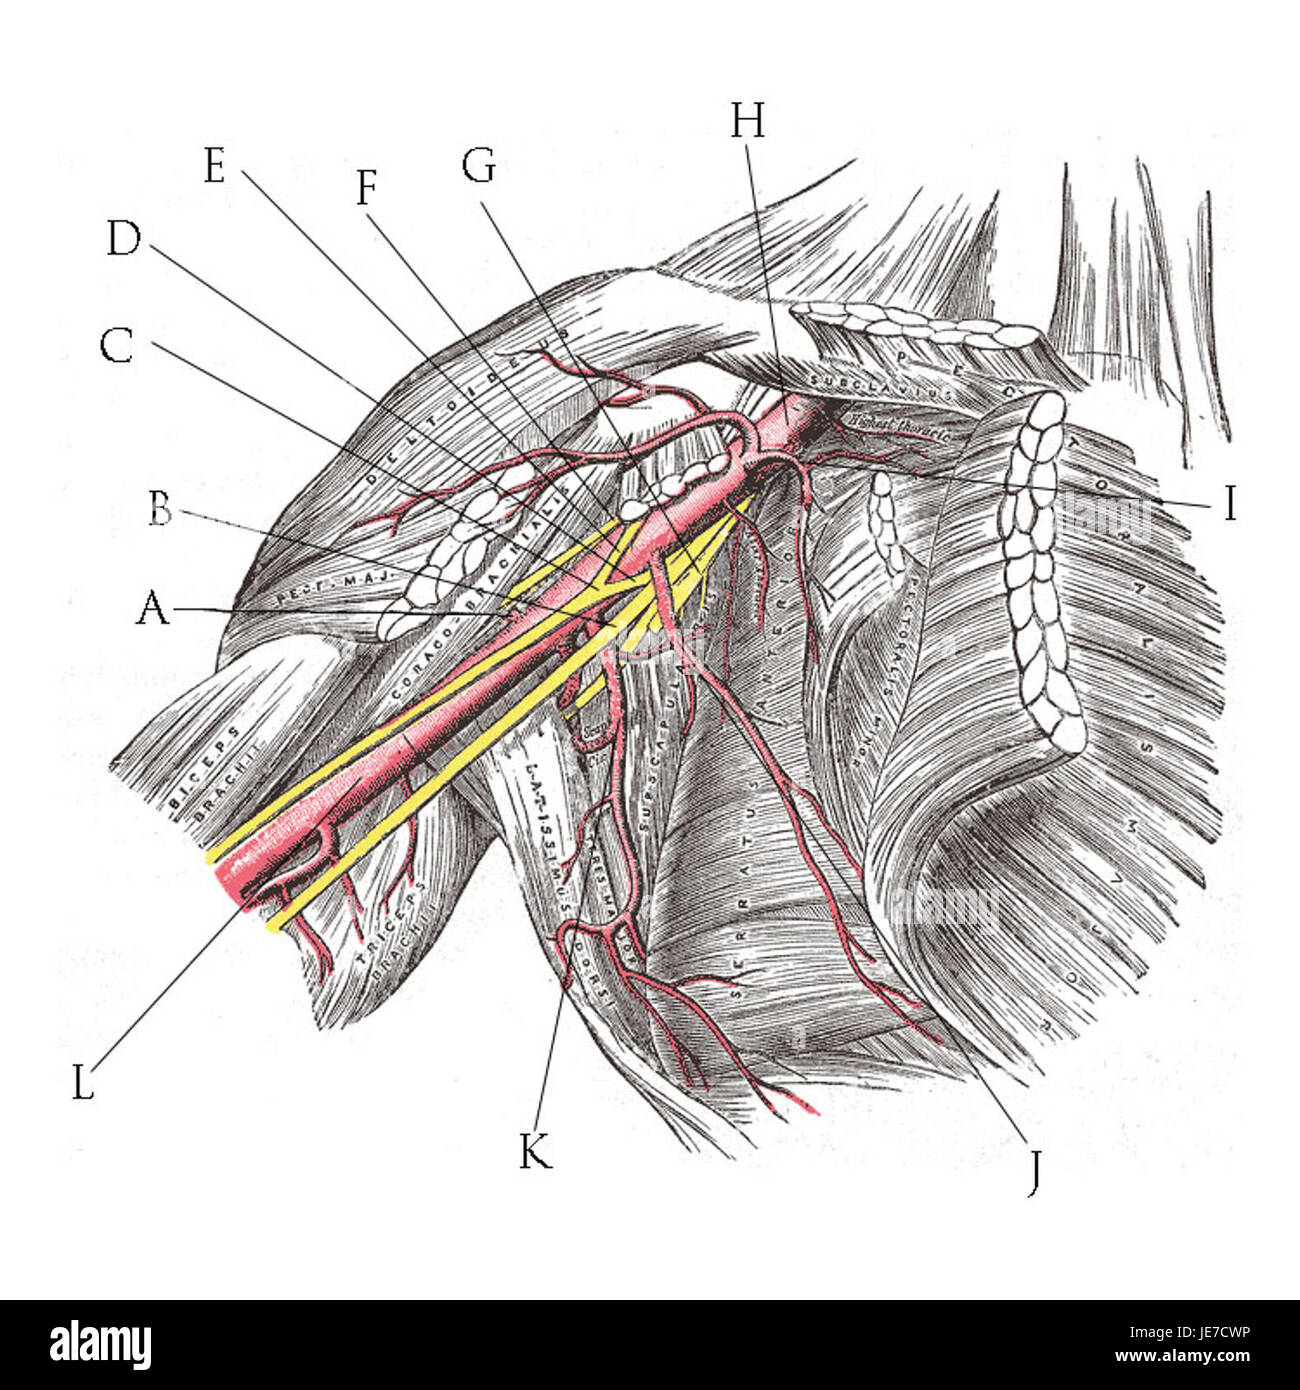

RMJE7CWP–Der Plexus brachialis ist ein Nervennetz im Nacken- und Schulterbereich, das für die motorischen und sensorischen Funktionen der oberen Extremität von wesentlicher Bedeutung ist. Das Bild zeigt den Plexus brachialis an seiner anatomischen Position.